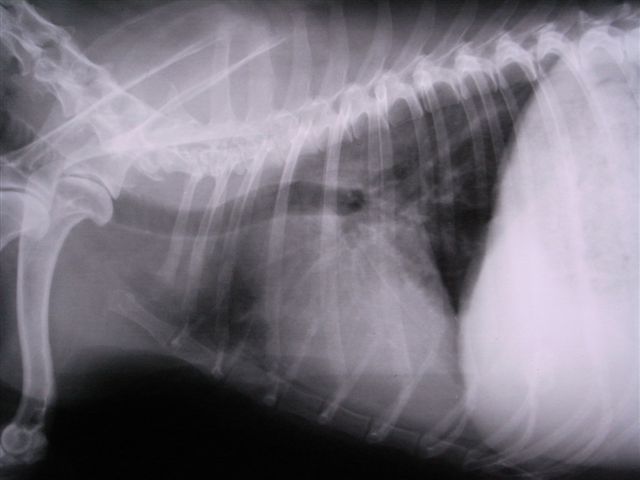

心臓の上部にしこり3cm大が確認できる そのため気管が蛇行している。気管の分岐部より後方は肺炎像がみられる。

2日後のレントゲン像

気管の蛇行は見られるが肺後部の肺炎像は小さくなった。